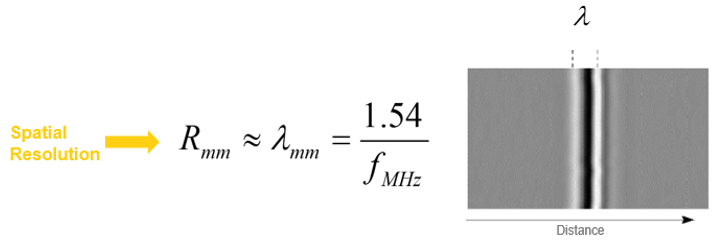

The resolution is defined as the ability to distinguish and identify two objects. It includes spatial and temporal resolutions. Spatial resolution is the ability to distinguish two separate objects that are close to each other. Whereas the temporal resolution refers to the ability to visualize moving objects. The main determinant of temporal resolution is the frame rate.

Spatial Resolution

Besides, the spatial resolution determines the degree of image clarity. It is divided into axial resolution, which is the capacity along the axis of the ultrasonic beam, and lateral resolution, which is perpendicular to the axis of the beam. The limit of the theoretical (spatial) resolution system is given by the wavelength of the ultrasound wave. The velocity of propagation in the soft tissues is about 1540 m/s.

Axial Resolution

The Axial Resolution is the minimum distance that can be differentiated between two reflectors located parallel to the direction of the ultrasound beam.

Mathematically, it is equal to half the spatial pulse length.

However, the Axial resolution is limited by the duration of the ultrasonic pulse. It is high when the spatial pulse length is short.

The axial resolution or the resolution in the direction of the axis of the ultrasonic beam depends on the duration of the ultrasonic pulse.